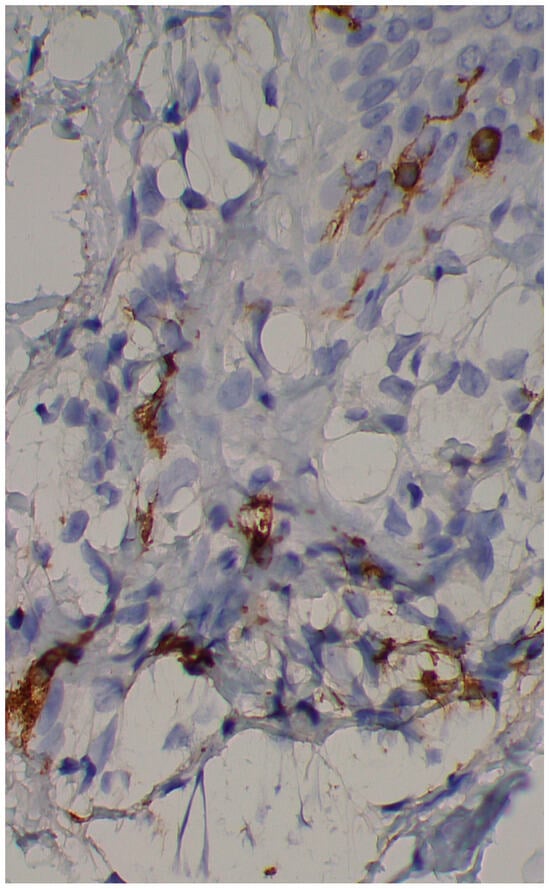

A skin biopsy showed basal cell hyperpigmentation and a chronic superficial perivascular inflammatory infiltrate that also affected the periphery of the hair follicles (Figure 6). Tryptase stain reached figures of up to 29 mast cells per high-power view (67/mm2), and CD117 up to 46 mast cells per high-power view (92/mm2), mostly surrounding the hair infundibulum (Figure 7), although some interstitial mast cells were also observed (Figure 8). PAS stain was negative for yeasts or fungal hyphae. Abdominal ultrasound study did not detect any anomalies. The bone scintigram detected mild non-specific osteoblastic lesions in the L5, S1 and sacroiliac joints (pending further study).

Figure 7. Mast cell infiltration in superficial dermis and around a pilosebaceous follicle (CD117 ×100).